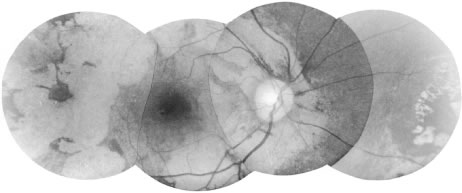

Clinically, the most common change is a granular atrophy of the retinal pigment epithelium often with intraretinal dispersion of pigment from the pigment epithelium22,23 (Fig. 11). Although areas of severe atrophy are easy to see, milder forms may only be revealed by fluorescein angiography. Chorioretinal atrophy is common and is usually associated with retinal pigment clumping (Fig. 12). Well-defined, white plaque-like areas of subretinal fibrosis with neovascularization may occur in these areas. Each of these three changes—retinal pigment epithelial atrophy, chorioretinal atrophy, and subretinal fibrosis—represents an end stage of, or the structural change caused by, previous acute inflammation induced either by the local death of microfilariae or possibly by other immune mechanisms.

Fig. 11. Discrete areas of retinal pigment epithelial atrophy are one of the most common fundal changes seen in onchocerciasis. Usually they occur temporal to the macula, but they may occur elsewhere. When seen through a hazy cornea, they may need to be differentiated from drusen.

Fig. 12. Large area of chorioretinal atrophy, which shows characteristic sparing of the uveal region until late in the disease.

Areas of active inflammation in the retina can sometimes be seen.23 They appear as areas of posterior retinal edema that demonstrate leakage of retinal capillaries and veins on fluorescein angiography. Pale, ill-defined areas of swelling in the choroid may also occur. These also show leakage on fluorescein angiography and are believed to be choroidal granulomas. Transitory retinal pigment epithelial abnormalities have also been seen with DEC therapy.24 A severe retinal vasculitis may rarely occur.

It is the variation in prominence and the distribution of each type of change that leads to the wide variation in the final morphologic picture. The extent of involvement is not clearly related to the severity of the infection. The macular region is often spared until late in the disease.